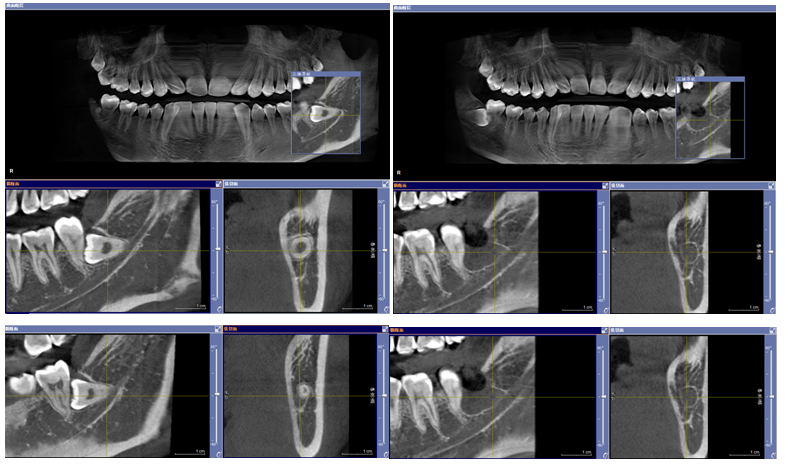

数字化导板技术:通过口腔 CT 扫描获取患者口腔颌骨的精确三维数据,利用计算机辅助设计(CAD)和计算机辅助制造(CAM)技术制作出个性化的手术导板。在牙槽外科手术中,如拔牙、种植牙等,导板可以精确引导手术器械的操作,提高手术的准确性和可预测性,减少手术创伤和并发症,同时缩短手术时间。

2、微创骨钉导航植入技术

采用CBCT三维定位结合口扫模型设计植入导板进行引导,避免微种植体植入时损伤牙根与神经,成功率大幅提升。

3、埋伏牙数字化导航开窗牵引

利用口腔扫描模型+CBCT三维定位,精确定位埋伏牙开窗位置,并设计牵引装置高效解决埋伏牙问题。